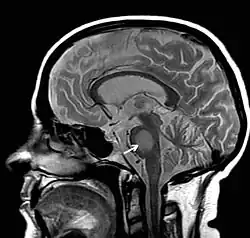

- Magnetresonanztomographie (Veränderungen oft erst nach einigen Wochen!)